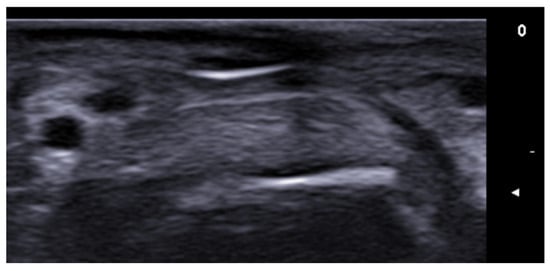

- Etesami, I.; Azizi, N.; Sabrinejad, R.; Montazeri, S.; Kamyab, K.; Nasimi, M.; Mahmoudi, H.; Khorasanizadeh, F.; Wortsman, X. Sonographic skin features and shear wave elastography in distinguishing active from inactive morphea lesions: A case-control study. J Am Acad Dermatol. 2025, 92, 155–157. [Google Scholar] [CrossRef] [PubMed]